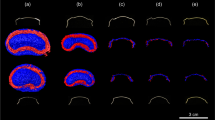

Each retainer was embedded in agar gel (Select Agar™, ThermoFisher Scientific; Waltham, MA, USA) in a cuboid plastic box. Next, in vitro MRI measurements were performed using a 3-Tesla (3 T) MRI system (MAGNETOM Trio TIM, Siemens Healthineers; Erlangen, Germany) with a 16-channel multipurpose coil (Variety, Noras MRI products; Hoechberg, Germany). For image acquisition, a T1-weighted, isotropic SPACE (sampling perfection with application-optimized contrasts using different flip-angle evolution) sequence optimized for 3D imaging of the craniomaxillofacial area was used [16]. Sequence parameters were as follows. Matrix: 256 × 256; field of view: 175 mm × 175 mm; voxel size: 0.68 mm × 0.68 mm × 0.68 mm; number of sections: 192; repetition time: 800 ms; echo time: 26 ms; bandwidth: 501 Hz/pixel; slice orientation: coronal; phase-encoding direction: right-to-left; number of averages: 2; echo train length: 63; GRAPPA (generalized autocalibrating partial parallel acquisition) acceleration factor: 2; time of acquisition: 6:59 min. Artifact volumes (AV) were quantified by means of semi-automated segmentation using Amira software (Version 6.4.0, ThermoFisher Scientific) as described elsewhere [36]. This standardized procedure enabled separate 3D identification of signal loss and core and pile-up artifacts. The artifact volume was obtained by adding the volumes of signal loss and pile-up artifacts and subtracting the retainer volume. The ratio of artifact volume to retainer volume (AV/RV ratio) was also calculated. Artifact diameters were measured perpendicular to the retainers’ longitudinal axes at the point with the largest diameter size. The workflow for in vitro MRI measurements and subsequent quantification of artifact volumes is shown in Fig. 2.

a, b Workflow for MRI measurement of retainers and subsequent quantification of artifact volumes. a Retainers were embedded in agar in plastic boxes. These boxes were then placed into a 16-channel multipurpose coil for in vitro MRI measurement at 3 T. b The primary image dataset is shown on the left, in which signal loss artifacts as well as the retainer itself appear hypointense (dark), and pile-up artifacts appear hyperintense (bright). After image acquisition, 3D volumes of hypointense (blue) and hyperintense regions (red) were defined by segmentation, as shown in the volume rendering on the right. Finally, the artifact volume was obtained by adding the volumes of hypointense and hyperintense areas and subtracting the retainer volume. MRI, magnetic resonance imaging; CAD/CAM, computer-aided design/computer-aided manufacturing

All four retainers caused susceptibility artifacts in the maxilla and mandible to a varying extent (Figs. 3 and 4). The largest artifact volumes were caused by the Twistflex retainers; total artifact volumes were 15,642 mm3 in the maxilla (AVmax) and 13,530 mm3 in the mandible (AVmand), of which 246 mm3 (1.6%) and 315 mm3 (2.3%), respectively, were pile-up artifacts. The AV/RV ratio for the maxilla (AV/RVmax) was 2235, compared with an AV/RV ratio for the mandible (AV/RVmand) of 2602. Maximum artifact diameters, measured perpendicular to the longitudinal axis of the retainers, were 32 mm in the maxilla and 28 mm in the mandible.

a–d Retainers with segmented representation of retainer and corresponding artifacts. Hypointense areas (signal loss artifacts and retainer itself) are in blue and hyperintense areas (pile-up artifacts) are in red. A reference line 3 cm in length is inserted on the bottom right. a Twistflex (stainless-steel alloy). b Cobalt–chromium. c Nickel–titanium. d Grade-5 titanium

Among the CAD/CAM retainers tested, the largest artifact volumes were recorded for the cobalt–chromium CAD/CAM retainers (although these volumes were still much smaller than those observed for Twistflex). Total artifact volumes were 394 mm3 (AVmax) and 381 mm3 (AVmand), of which pile up-artifacts were 12 mm3 (3.0%) and 38 mm3, respectively. The corresponding ratios of artifact volume to retainer volume were 31 (AV/RVmax) and 39 (AV/RVmand). Artifact diameters perpendicular to the longitudinal axis of the retainers reached maximum values of 9 mm (maxilla) and 8 mm (mandible).

For the grade-5 titanium CAD/CAM retainers, AVmax was 126 mm3, and AVmand was 110 mm3. The corresponding pile-up-artifacts were 17 mm3 (maxilla) and 43 mm3 (mandible). AV/RVmax and AV/RVmand ratios were 11. Artifact diameters perpendicular to the longitudinal axis of the retainers were 4 mm for both the maxilla and for the mandible.

The nickel–titanium CAD/CAM retainers caused the smallest total artifact volumes of all three CAD/CAM retainers, with an AVmax value of 78 mm3, and an AVmand value of 54 mm3, of which 9mm3 (11.5%) and 8mm3 (14.8%) were pile-up artifacts, respectively. The AV/RVmax ratio was 14, compared with the AV/RVmand ratio of 12. Measurements perpendicular to the long axes of the retainers revealed maximum artifact diameters of 3 mm in both the maxilla and mandible.